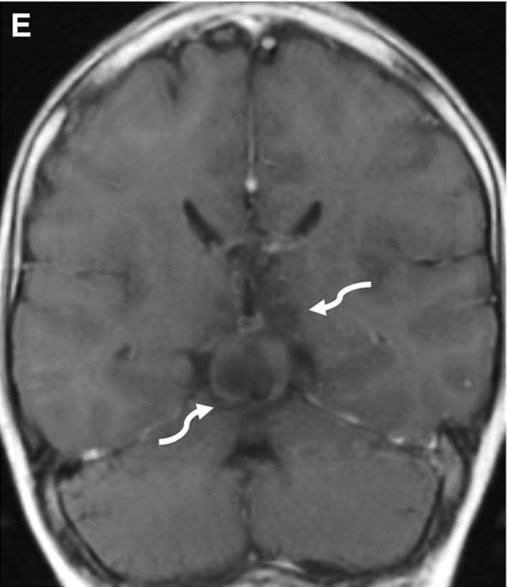

c. Lipomatose encéphalocraniocutanée (ECCL): peau, yeux, SNC)

ECCL: